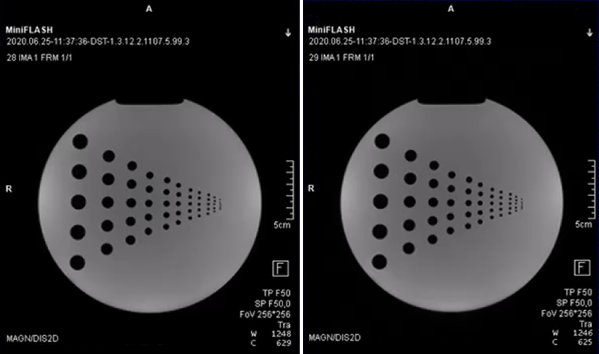

The prototype FLASH sequence and various deployment options successfully have been validated against the vendor's original implementation utilizing a sequence-diagram-based validation toolkit introduced earlier6. The scanner integration was successful, and images acquired with the prototype FLASH sequence show no visible differences to the original, see Figure 5.

The resulting images of the phantom scan. The left image shows the reconstructed image of the FLASH sequence directly implemented in the vendor’s software development environment. The right image shows the reconstructed image of the prototype FLASH sequence developed as Remote Sequence utilizing the commands provided by the interface. Both images were reconstructed using the same image reconstruction pipeline at the scanner.